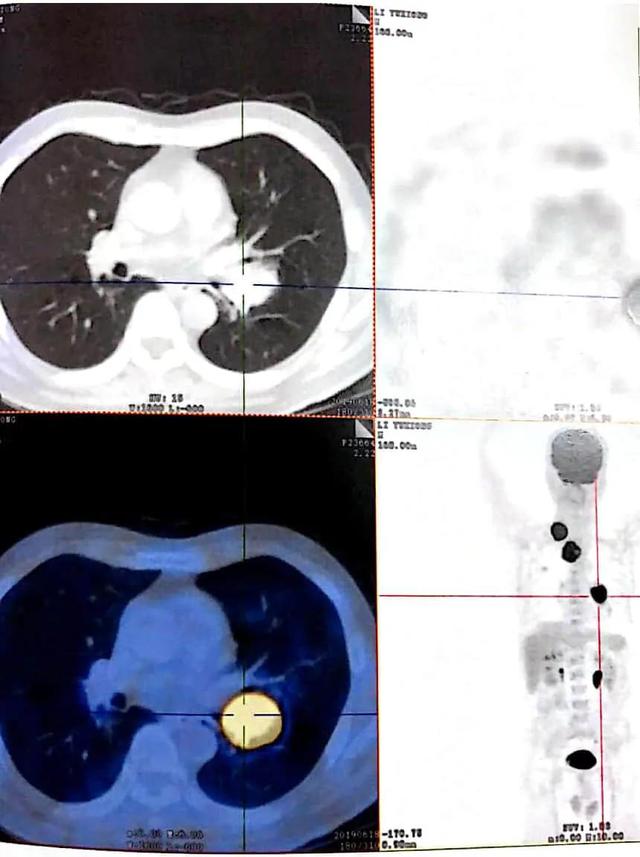

手术前CT

罗鹏飞教授、王健主任团结 患者既往病史、辅助检查效果 ,明确诊断为:肺恶性肿瘤(左下肺低分化非角化性鳞癌 T3N3MO IIIB期)。确定病症后,凭证 李大爷的现实 病情罗教授制订 了一套完整的治疗方案,治疗上继续予以抗肿瘤、营养支持,最后手术治疗扫除 病灶,行双侧支气管动脉造影、凭证 造影情形 予灌注及栓塞治疗;到达减瘤控制肿瘤继续生长的效果。